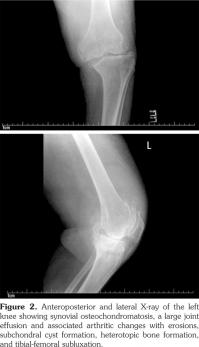

Plain radiographs of the knee joints revealed joint effusions with multiple rounded intra-articular loose bodies, erosions on the medial aspect of the tibial plateau, tricompartmental joint space narrowing, osteophytes, subchondral cyst formation, heterotopic bone formation, and lateral subluxation of the tibia on the femur (Figure 1, 2).

The patient was diagnosed with SOC, based on the presentation with chronic oligoarticular synovitis in the knees, and the X-ray findings. The consulting rheumatology and orthopedic services recommended conservative management due to the patient’s global health status, and in accordance with her wishes. The patient was subsequently transferred to a nursing home with instructions to use hinged knee braces.